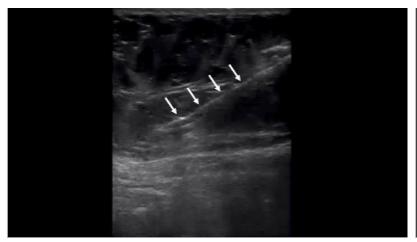

Cadaveric Validation Following lipoaspiration, the cannula was maintained in the harvest site, and 3 mL of colored latex was injected under ultrasound guidance into the aspirated adipose layer. Subsequent cadaveric dissection was performed to assess latex distribution and to verify that the aspiration tracts remained confined to the adipose tissue, without penetration into muscular or peritoneal structures.

Microscopic analysis of the aspirated tissue revealed “grape-like clusters” of very large cells (~100 micron) with no discernable nucleus in the center of the cytoplasm, characteristic of adipose tissue. All six samples following centrifugation had a compacted appearance. Any tissue dispersion would have been indicative of connective tissue rather than adipose tissue. All six samples post-centrifugation had tissue floating above the saline solution, indicating the tissue density was less than 1.0046 g/mL (the density of normal saline solution at 22° C). This lower density tissue is characteristic of adipose, which has a density between 0.925-0.970 g/mL. All samples appeared to contain adipose tissue with no evidence of peritoneal or muscular tissue. With cadaver dissection, all colored latex injections were found within the targeted adipose tissue layer of the anterior abdomen of the three cadavers.

The dual validation method used in this study—microscopic analysis to confirm tissue type, and colored latex dissection to verify anatomical targeting—adds rigor to the findings. The latex injections demonstrated that all six aspiration tracts remained within the adipose layers, without extension into muscle or peritoneal tissue. This mirrors validation methods previously used in studies of ultrasound-guided joint, nerve, and spinal procedures and offers proof of concept for the reproducibility of this technique.